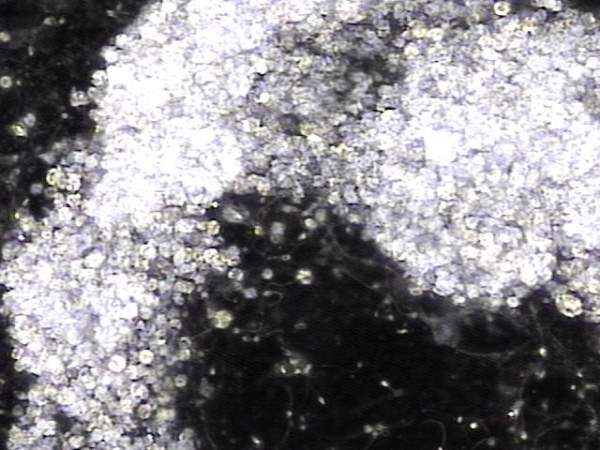

내원당일 전립선의 표적 치료후 배양과 전립선액의 PCR 검사를 위해 채취하고 검사한 현미경학적 확대 사진입니다.

A high-magnification microscopic image taken on the day of the visit, following targeted prostate therapy,

showing the prostatic fluid sample collected for culture and PCR testing.